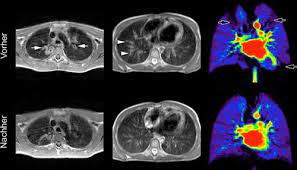

Fruhdiagnose Und Therapiekontrolle Bei Mukoviszidose

Fruhdiagnose Und Therapiekontrolle Bei Mukoviszidose from www.mta-dialog.de

Computertomographie Der Lunge Bei Mukoviszidose Springerlink

Computertomographie Der Lunge Bei Mukoviszidose Springerlink from media.springernature.com